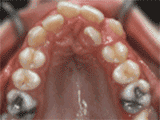

牙列擁擠,牙槽骨過窄,牙齒沒有足夠空間,只好前后左右高低上下亂長,經(jīng)過矯正后的牙齒是這樣的~